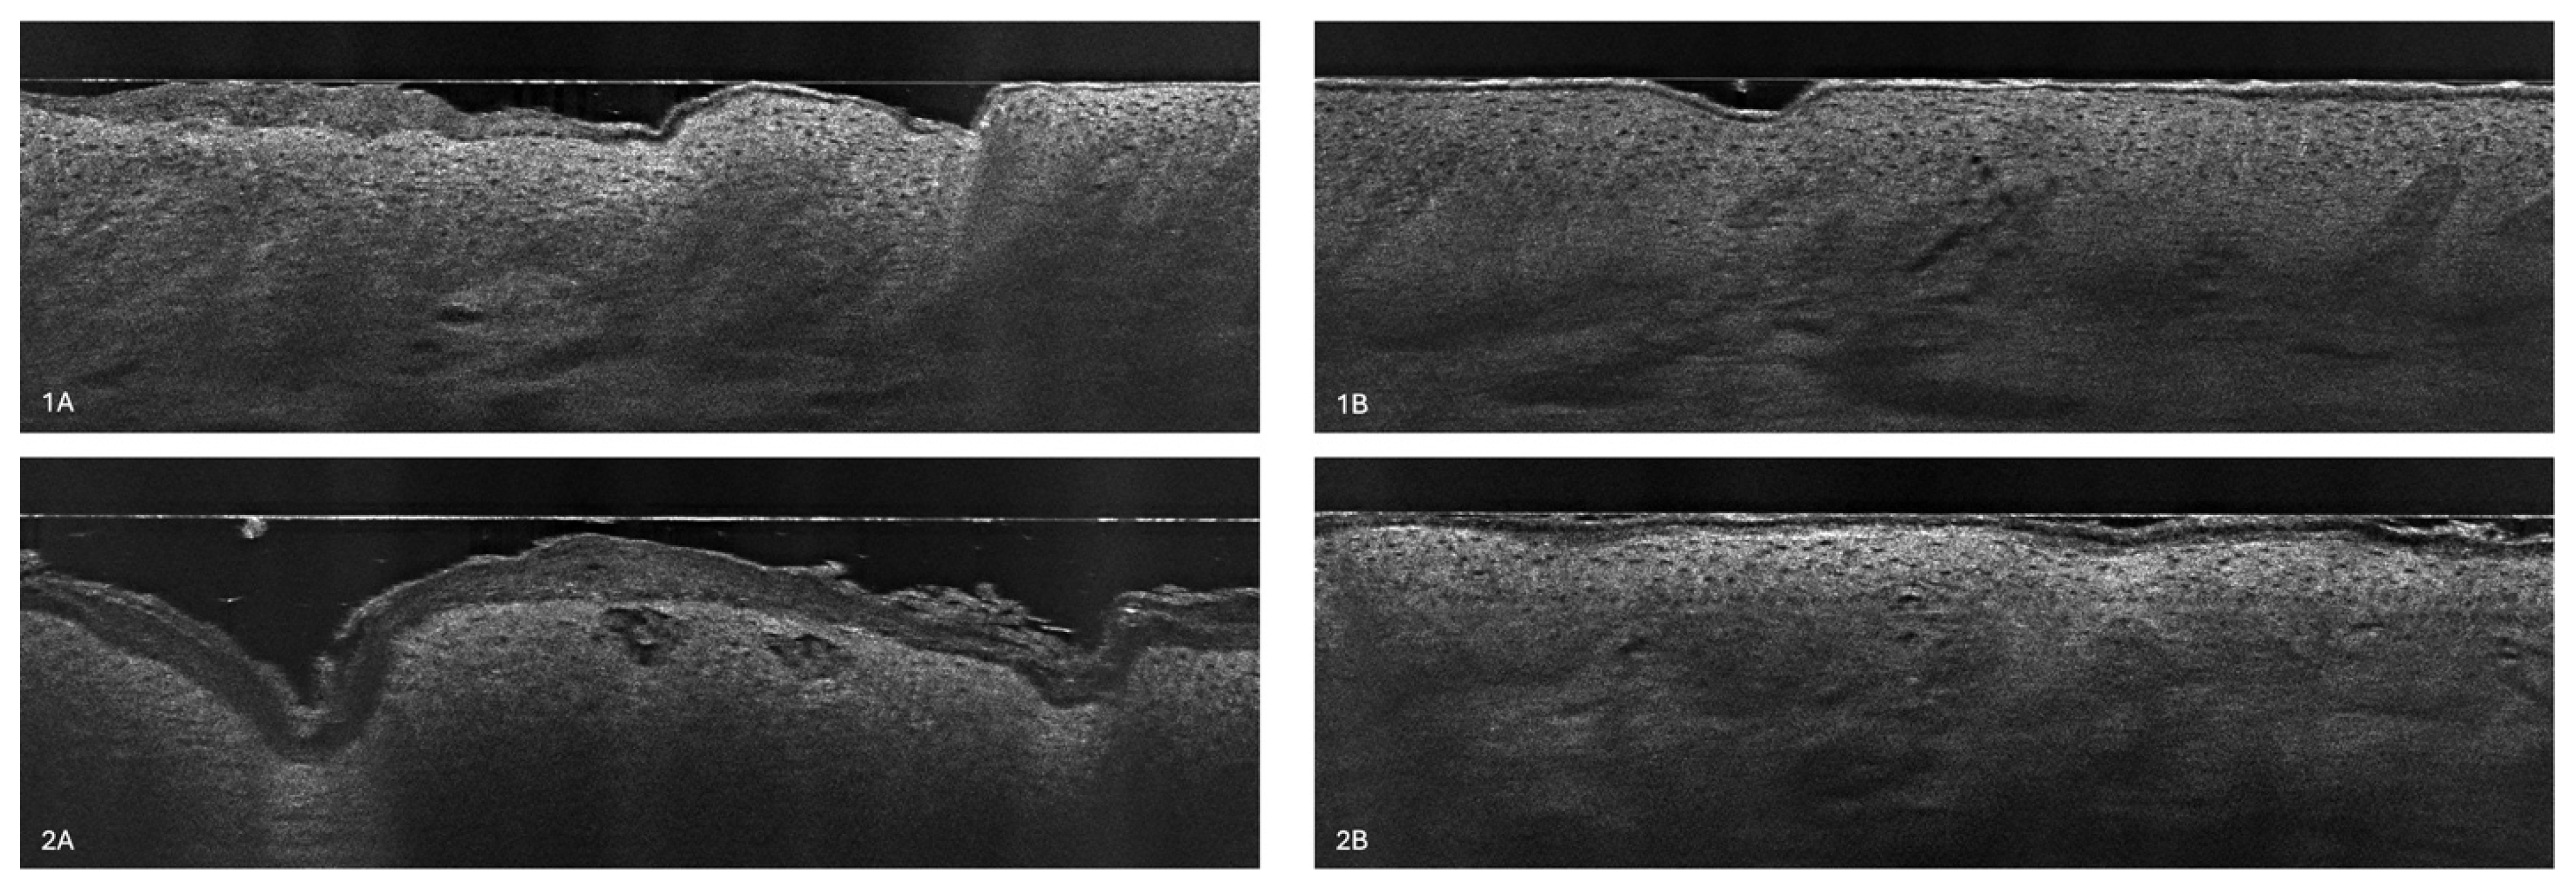

3.1. Atopic Dermatitis in LC-OCT

3.2. Stratum Corneum Thickness

3.3. Stratum Corneum Disturbances

3.4. The Epidermal Thickness